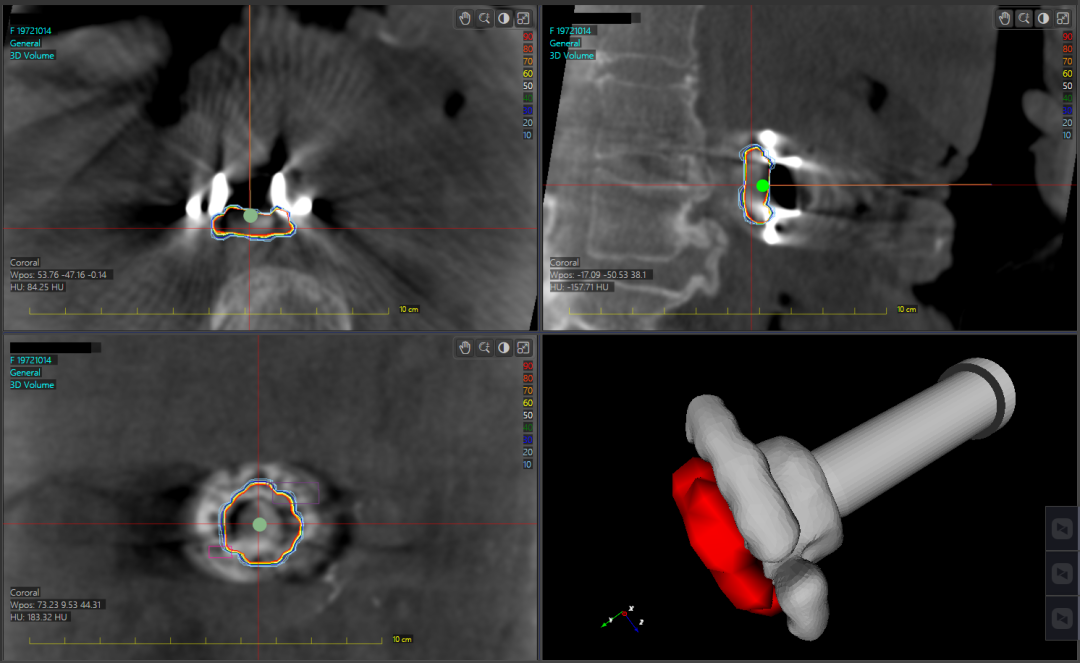

基于术中实时CT,对瘤床和复发风险较高区域快速勾画,计算并得到三维图像和剂量分布;

基于以上优势以及医院具备的国际先进设备与技术,治疗团队自主研发了一套基于术中CT三维成像的三维术中放疗计划系统,通过这套系统,医生能够在手术过程中,准确判断术中放疗的区域并进行靶区的勾画,还能够直观看见术中放疗部位与复发风险较高区域的三维剂量分布信息,从而更准确、高效的判断术中放疗效果,还能更细致地保护周围组织器官。

10月18日,三维术中放疗计划系统首次应用于临床,郝继辉院长带领团队,为一名胰腺癌患者,开展了全球首例移动式CT图像引导的胰腺癌术中精准放疗。该患者肿瘤位置靠近重要血管,后期的体外放疗难以做到精准定位和重要组织保护。结合患者治疗方案,治疗团队术中将肿瘤完整切除后,利用C形臂CT实现瘤床区域的三维快速成像。通过三维术中放疗计划系统,实时观察并调整患者术中放疗实施方案,同时还保证了术中放疗施用器在靶区的位置准确性。在团队的整体密切配合下,术中放疗顺利实施,手术成功完成。患者术后恢复良好,将于近期出院。